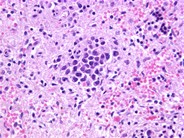

Intravascular Large Cell Lymphoma - 2.

Category: Lymphoma: Mature B-cell and Plasma cell Neoplasms > Large B-cell lymphomas (not Richter transformation) > Intravascular large B-cell lymphoma

The lymphoma cells are large with irregular nuclear contours, clumped chromatin, and prominent nucleoli. These cells were immunoreactive for pan B-cell markers CD20 and CD79a.